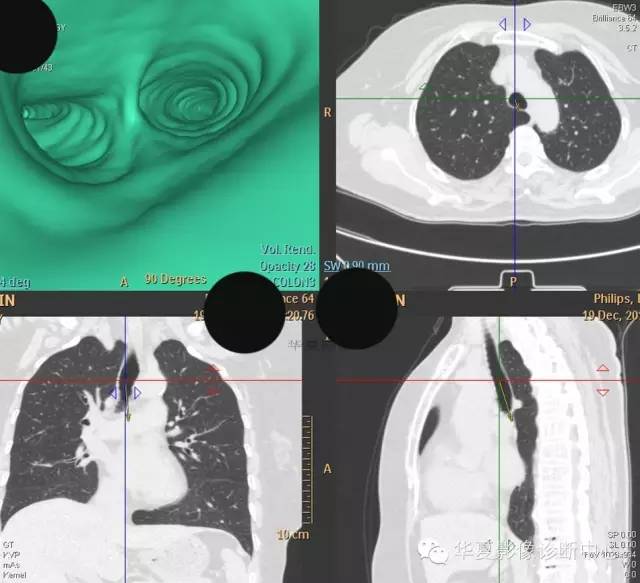

【病例学习】典型周围型肺癌CT病例一例

女,56岁,其父因肺癌去世,自觉胸部疼痛不适来诊要求拍胸片。

检查所见:

1.右肺上叶:肺组织1块,大小13×4×7cm。切面棕红色。2.右肺上叶肿物:灰白色组织一块,大小3×1×1.5cm。切面灰白色。3.右肺中叶结节:灰白色绿豆大组织1块。4.淋巴结:灰黑色绿豆大组织1块。

检查结论:

(右)肺中分化鳞状细胞癌。浸及胸膜。支气管残端切净。淋巴结未见癌转移(0/10)。